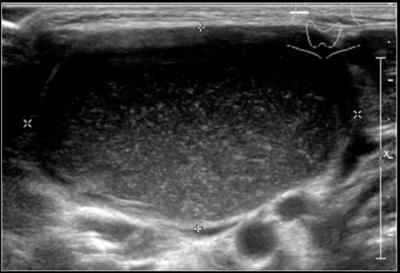

Yeni doğan bebeklerde doğum şekli eğer normal yoldan ancak zorlu bir şekilde olmuşsa, zorlanmaya bağlı olarak bebeğin boynunda kas zedelenmeleri oluşmuş olabilir. Genellikle ilk aylarda bebeğin boynunun bir tarafa eğik durması ya da o tarafa kafasını çok çevirmemesi gibi bulgulara yol açabilir. Bu durumu tortikollis olarak adlandırırız. Boynun iki yanında kafamızı sağa ya da sola çevirmemizi sağlayan kas gruplarımız vardır. Zorlu doğumlarda bu kaslar içerisinde kanamalar ya da yırtıklar oluşabilir. Bu kanama veya yırtıkları değerlendirmek için mutlaka ultrason incelemesi yapılmalıdır. Ultrason incelemesi ile saptanan bu kas hasarlarının ileride hareket problemlerine yol açmaması için tedavisi gerekir. Medikal tedavi ve fizik tedavi yöntemleriyle kastaki hasar giderilir.